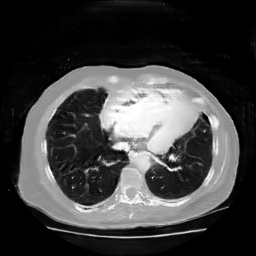

The study utilizes three 3D datasets, namely the GSP dataset[3], the LIDC-IDRI dataset[1], and the dataset employed for the Lung Nodule Analysis 2016 (LUNA16) challenge[21] which is a subset of LIDC-IDRI dataset. Samples from generated images at different stages of training are presented in Fig. 2 and Fig.3.

Refer to caption

20000

30000

40000

50000

60000

70000

80000

CRF-GAN synthetic images at different iterations

HA-GAN synthetic images at different iterations

Figure 3: Synthetic images of CRF-GAN and HA-GAN at different iterations of training on the LUNA16 dataset